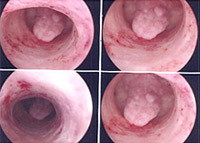

Εικόνα οξείας ενδομητρίτιδας

- για την ύπαρξη περιοχών με φλεγμονή, είτε με λοίμωξη όπως οι σπάνιες περιπτώσεις ενδομητρίτιδας,

- η ύπαρξη κάποιων περιοχών με ατελείς συμφύσεις ή διάφραγμα

Εικόνα ενδομητρικού διαφράγματος